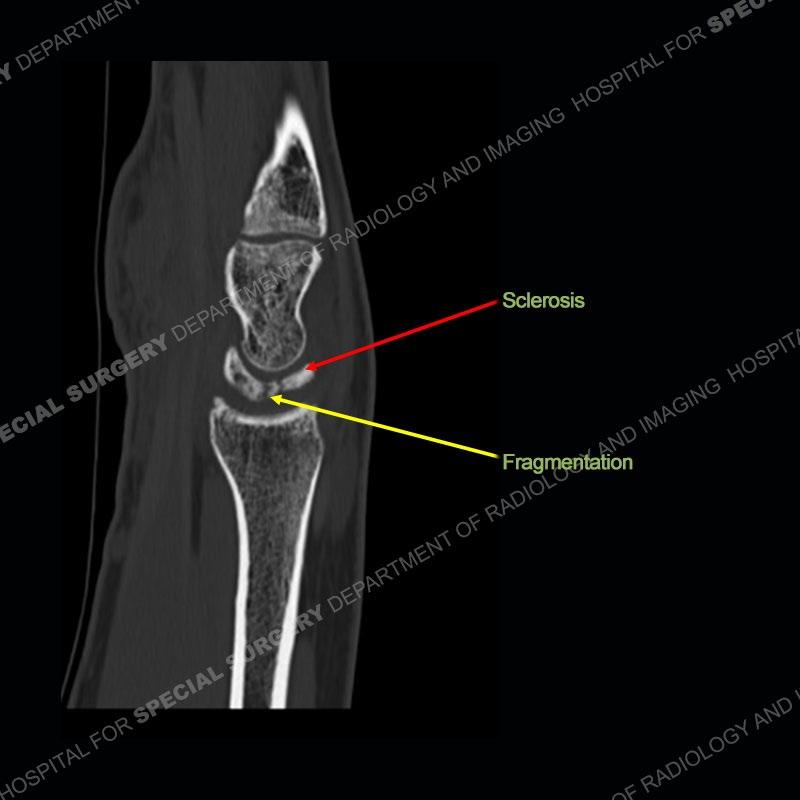

Both cases demonstrate similar findings to slightly less and more conspicuous degrees. The radiographs show sclerosis and fragmentation/collapse of the lunate. The CT images for case one just further clarify the architecture of the lunate. The MRI images show a slightly greater degree of variability but with overall persistent areas of low signal of the lunate on all pulse sequences and with a loss of the geometry of the lunate indicating collapse and fragmentation.

A well recognized but still poorly understood entity with necrosis and collapse representing the end stage of the pathology. The reasons for the necrosis are likely multifactorial and relate to the anatomy of the wrist inclusive of ulnar variance and the anatomy of the vasculature to the lunate. Other inflammatory, biological processes and overuse/trauma also likely play a role in the development of the necrosis. The disease manifests by sclerosis of the lunate followed by collapse and fragmentation. This is then followed by abnormal orientation of the scaphoid in a palmar flexed position and then adjacent arthritis. These latter processes were not the focus of this case presentation. The MRI will show areas of low signal on all pulse sequences indicating the areas of devitalized bone. The foci of slightly increased signal are in keeping with areas of maintained perfusion and highlight the variable architecture and findings of Kienbock’s. The fragmentation and collapse of the bone are seen well on both CT and MRI.